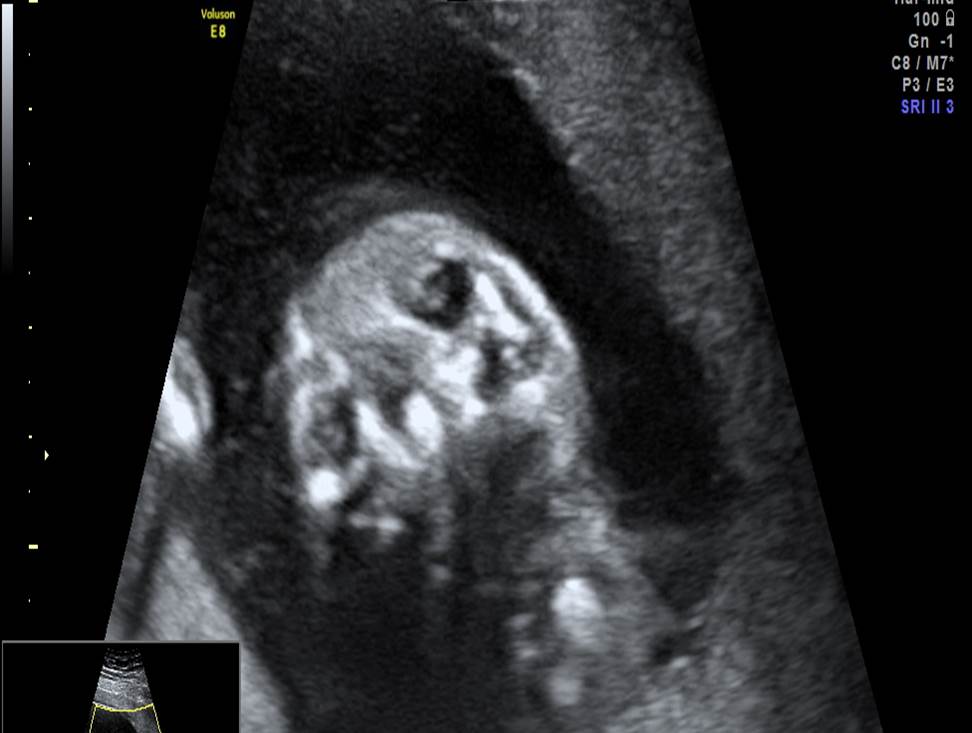

Проанализируйте изображения и видео-клипы плода в 20 недель, установите диагноз

Пациентка обратилась для получения второго мнения с диагнозом: беременность 20 недель, гипоспадия. Проанализируйте изображения и видео-клипы плода в 20 недель, установите диагноз